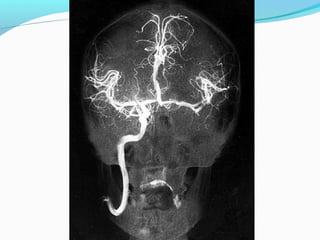

-O encéfalo é irrigado basicamente por dois sistemas:

- carotídeo

- vertebral

- Essas artéria formam o Polígono de Willis de onde partem as principais

artérias para a vascularização cerebral.

- Direita e Esquerda que se destacam das Artérias

Subclávias

- Sobem no pescoço dentro dos Forames Transversos das

Vértebras Cervicais.

- Penetram no Forame Magno ao atravessarem a membrana

Atlanto-Occipital, Dura-Máter e Aracnóide.

- Fundem-se para formar a Artéria Basilar

- As Vertebrais originam também as Artéria Espinhais

Posterior e Anterior além das Cerebelares Inferiores

Posteriores

- A Artéria Basilar bifurca-se nas Artérias Cerebrais

Posteriores Direita e Esquerda

- Ramos da Basilar:

a. Artéria Cerebelar Superior

b. Artéria Cerebelar Inferior Anterior

c. Artéria do Labirinto

-O encéfalo éirrigado basicamente por dois sistemas: - carotídeo - vertebral - Essas artéria formam o Polígono de Willis de onde partem as principais artérias para a vascularização cerebral. -- Artérias finas como veias propensas a hemorragias - Túnica média com menos fibras musculares - Túnica elástica interna mais espessa e tortuosa: amortece a pulsação arterial.

- Direita eEsquerda que se destacam das Artérias Subclávias - Sobem no pescoço dentro dos Forames Transversos das Vértebras Cervicais. - Penetram no Forame Magno ao atravessarem a membrana Atlanto-Occipital, Dura-Máter e Aracnóide. - Fundem-se para formar a Artéria Basilar - As Vertebrais originam também as Artéria Espinhais Posterior e Anterior além das Cerebelares Inferiores Posteriores

- A ArtériaBasilar bifurca-se nas Artérias Cerebrais Posteriores Direita e Esquerda - Ramos da Basilar: a. Artéria Cerebelar Superior b. Artéria Cerebelar Inferior Anterior c. Artéria do Labirinto